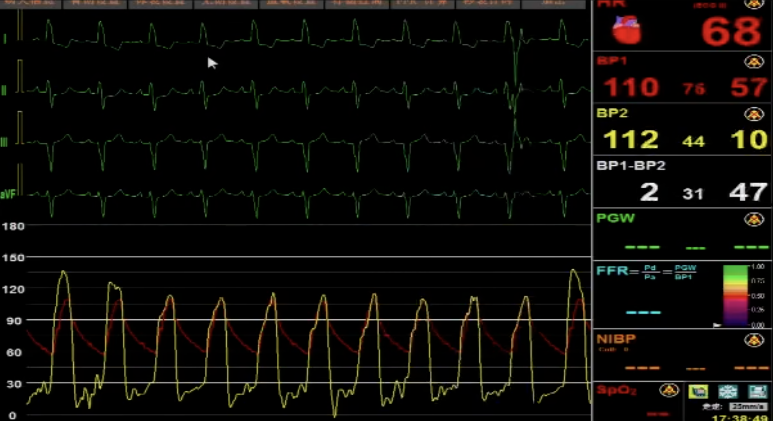

导管测压,压力阶差60mmHg:

术后导管测压压差为2mmHg: